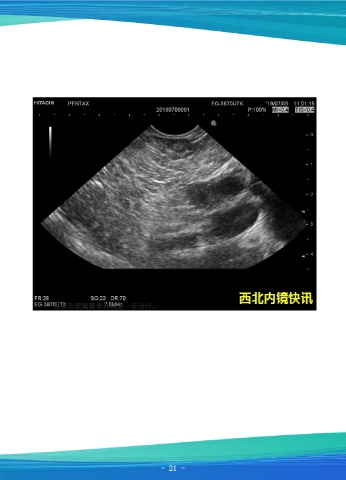

一例早期胰腺癌

患者男,38岁,因“间断上腹痛半年”就诊,行上腹部CT检查示:主胰管扩张,胰

腺实质萎缩,建议MR及MRCP进一步检查,肝小囊肿,肝右叶钙化灶。超声内镜示:慢

性胰腺炎,胰腺假性囊肿。门静脉增强CT:门静脉略增宽,肝包膜下小脂肪瘤,胰腺多

发囊性病灶,多囊胰?胰管扩张?胰腺MR检查:胰腺信号欠均匀,主胰管呈串珠样显著

扩张,并胰尾部多发囊性灶,建议增强检查;腹膜后多发肿大淋巴结。

于我院行超声内镜下行胰头占位穿刺活检。活检病理回报:高度怀疑神经内分泌肿

瘤。